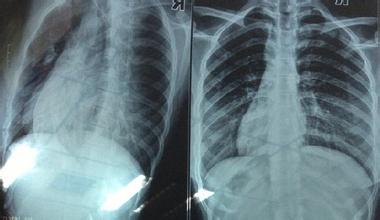

我院成功治愈多根多處肋骨骨折

多根多處肋骨骨折常由巨大暴力所致,胸廓外形發(fā)生改變,以胸部疼痛、呼吸困難為主要表現(xiàn),常合并有肺挫裂傷、血?dú)庑氐龋植炕顒?dòng)胸壁可隨呼吸出現(xiàn)矛盾運(yùn) 動(dòng),約占肋骨骨折的5%,可危及生命。早期,疼痛以及胸廓穩(wěn)定性受破壞,可使呼吸動(dòng)度受限、呼吸淺快和肺泡通氣減少,病人不敢咳嗽,痰潴留,從而引起下呼 吸道分泌物梗阻、肺不張或感染,呼吸衰竭,這在老弱病人或原有肺部疾患的病人尤應(yīng)予以重視。后期,肋骨畸形愈合,造成肋間神經(jīng)長(zhǎng)期受壓,患者長(zhǎng)期受到肋間 神經(jīng)痛的困擾,嚴(yán)重影響生活質(zhì)量,治療效果欠佳,胸廓畸形,肺容量縮小,肺活量部分喪失,影響工作生活。所以,手術(shù)治療進(jìn)行干預(yù),在多根多處肋骨骨折的治 療中顯得尤為重要。

通過(guò)對(duì)病人的術(shù)后隨訪,復(fù)查肋骨對(duì)位好,雙側(cè)胸廓對(duì)稱,胸壁無(wú)塌陷,呼吸良好,疼痛明顯減輕,無(wú)1例傷口感染,患者基本恢復(fù)正常,行胸部CT及相關(guān)核磁共振檢查均不受影響,全組無(wú)一例有排異不適等需取出者。